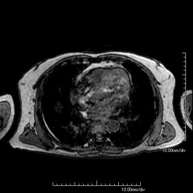

Prova diagnòstica no invasiva que consisteix en l'obtenció d'imatges d'alta definició anatòmica del mediastí mitjançant l'ús d'un camp electromagnètic i ones de ràdio (amb un emissor i un receptor). No utilitza radiació ionitzant. El mediastí és la part central de la caixa toràcica que inclou el tim, els grans vasos (aorta toràcica, vena cava inferior i superior, etc.), el cor, la tràquea i els bronquis principals, els ganglis limfàtics mediastínics i hilars, l'esòfag, etc. Està especialment indicada en lesions mediastíniques per diferenciar si són quístiques o sòlides, en el diagnòstic diferencial de les lesions del mediastí anterior, etc. De vegades s'ha d'emprar contrast paramagnètic (Gadolini) per completar l'estudi. - RM Tòrax

Prova diagnòstica no invasiva que consisteix en l'obtenció d'imatges d'alta definició anatòmica del tòrax mitjançant l'ús d'un camp electromagnètic i ones de ràdio (amb un emissor i un receptor). No utilitza radiació ionitzant. Està indicada en aquelles lesions pulmonars en les quals s'ha de descartar si hi ha infiltració del mediastí o de la paret toràcica, per diferenciar si una lesió toràcica és sòlida o quística, etc. En alguns casos caldrà emprar contrast paramagnètic (Gadolini) per completar l'estudi. - RM de Paret Toràcica

Prova diagnòstica no invasiva que consisteix en l'obtenció d'imatges d'alta definició anatòmica de la paret toràcica mitjançant l'ús d'un camp electromagnètic i ones de ràdio (amb un emissor i un receptor). No utilitza radiació ionitzant. Està indicada en l'estudi de lesions de paret toràcica: costals, esternals, musculars (pectorals, intercostals, paravertebrals, etc.), en l'estudi de dolors costals, etc. En alguns casos caldrà emprar contrast paramagnètic (Gadolini) per completar l'estudi. - Angio-RM d'Aorta Toràcica